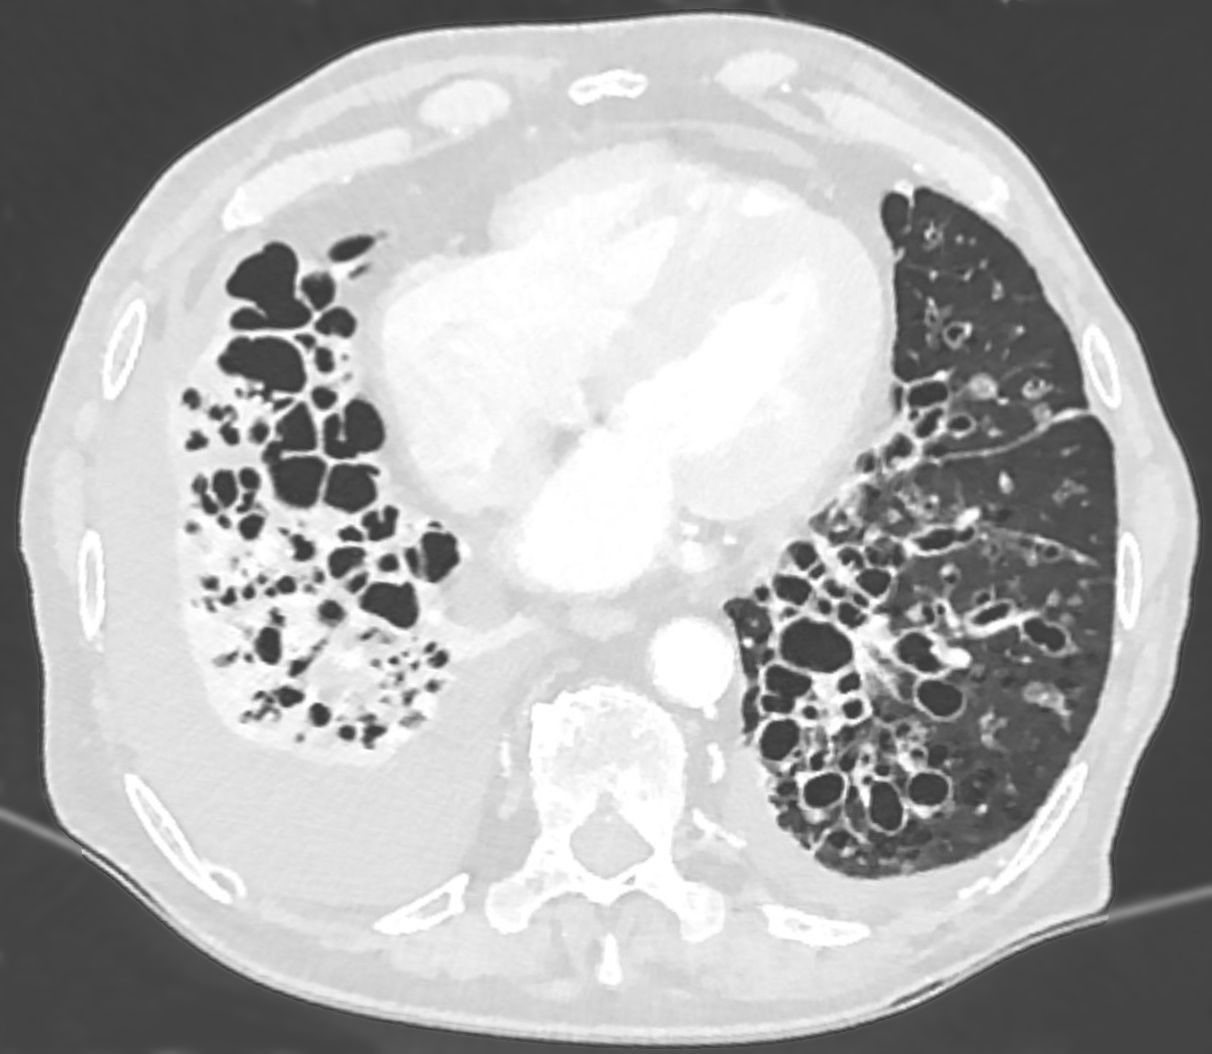

High-Resolution CT Thorax (HRCT) [3,7]

Indications (Not routine for acute exacerbation):

- Initial bronchiectasis diagnosis (gold standard)

- Severity assessment and extent mapping

- Baseline for surgical planning

- Suspected complications (abscess, empyema)

- Atypical presentation or treatment failure

- Assessment of underlying cause (nodular pattern in NTM/ABPA; upper lobe in CF)

Diagnostic Criteria:

- Broncho-arterial ratio > 1.5 (dilated bronchus compared to adjacent pulmonary artery)

- Lack of bronchial tapering: Bronchi visible to periphery

- Bronchial wall thickening

- Mucus plugging: Tree-in-bud pattern

Bronchiectasis Distribution:

| Pattern | Suggests |

|---|---|

| Upper lobe predominant | CF, ABPA, post-TB, sarcoidosis |

| Lower lobe/bilateral | Post-infectious, idiopathic, aspiration |

| Central (varicose) | ABPA |

| Nodular/tree-in-bud | Mycobacterial (NTM), aspiration |

HRCT Severity Scoring Systems [7]:

Modified Reiff Score (0-18):

- Extent of bronchiectasis (0-3 per lobe x 6 lobes)

- Severity of bronchial dilation (mild/moderate/severe)

- Mucus plugging

Higher scores correlate with:

- Increased exacerbation frequency

- Worse lung function

- Higher mortality